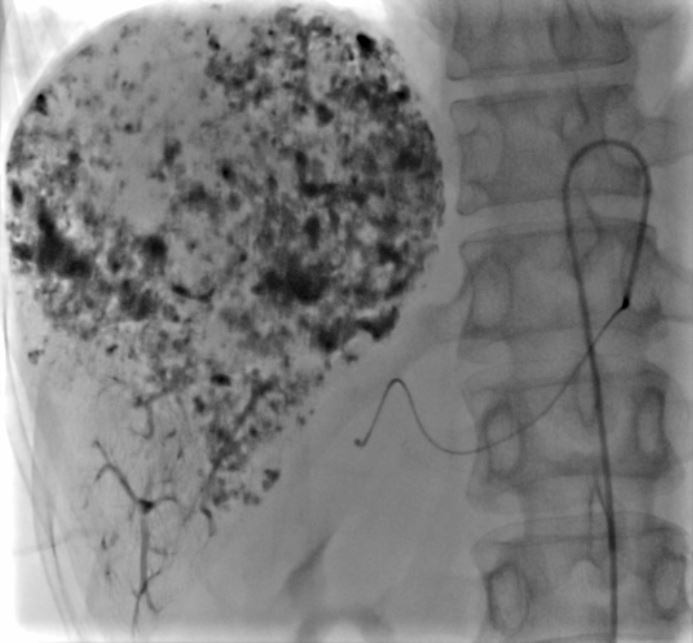

近日,潞河医院介入疼痛科为一名巨大肝血管瘤女性患者成功实施了介入栓塞治疗。患者梁女士今年49岁,体检时发现肝右叶血管瘤,最大径约9.6cm,且位于肝脏边缘,虽然破裂的几率较小,但一旦自发或外伤性破裂可能会给患者带来致命后果。梁女士入院后,介入疼痛科主任韩洋带领团队认真评估了术前影像学检查,并完善各项检验,排除治疗禁忌后,讨论制定了治疗方案。在与梁女士及家属充分沟通后,介入团队为其成功实施了微创介入栓塞治疗。术中腹腔干及肝动脉造影可见肝右叶巨大肿瘤染色,随着栓塞治疗的持续,可见该血管瘤内药物逐渐沉积,治疗完毕后再次造影显示原肿瘤供血动脉已封堵。手术成功完成,达到了治疗目的。术后,梁女士没有出现任何不良反应,现已顺利出院。

打药快结束